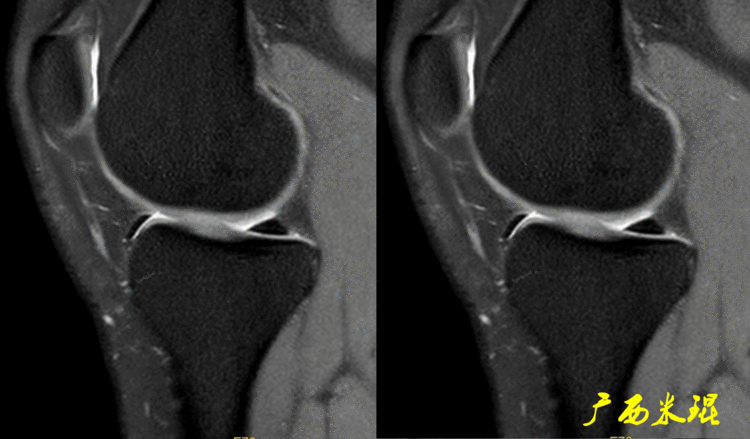

如同下面这张MR,左侧图像为手术前的,右侧图像为手术后的,术后病人疼痛等症状仍然存在,复查MR见外侧半月板前角分层,半月板前角的处理是有一定难度的,有经验的医生会考虑可能是手术者对前角的处理不够熟悉,没有通过另外的办法处理半月板前角的水平裂,不过也只能是猜测而已。所以,对于半月板术后的评估,症状的消失比MR重要!